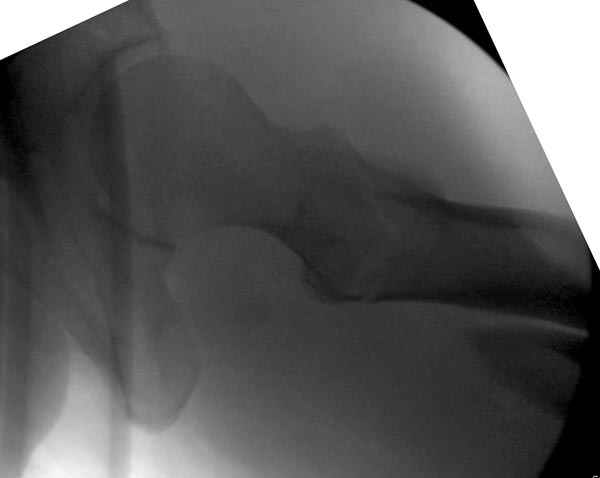

Второй случай тоже репозиция из малого доступа, больному 19 лет, множественные огнестрельные повреждениия конечностей, живота и черепа, правая конечность холодная, без пульсации. Ортопедический диагноз: огнестрельный перелом правого бедра. При срочной ангиографии повреждения сосудов не подтвердилось, конечность из-за ургентности состояния больного зафиксирована временным наружным фиксатором и больной оставлен на операционном столе для срочной лапаротомии хирургической службой.

Больной долго оставался нестабильным, только на 14 день удалось заменить на антеградный интромедуллярный штифт TFN (trochanteric femoral nail) SmithNephew. После неудачной попытки закрытой репозиции, несмотря на использование "joystick", проксимальный стержень от

наружного фиксатора, (перелом начал срастаться) репозицию провели из малого доступа, затем остальные этапы операции.